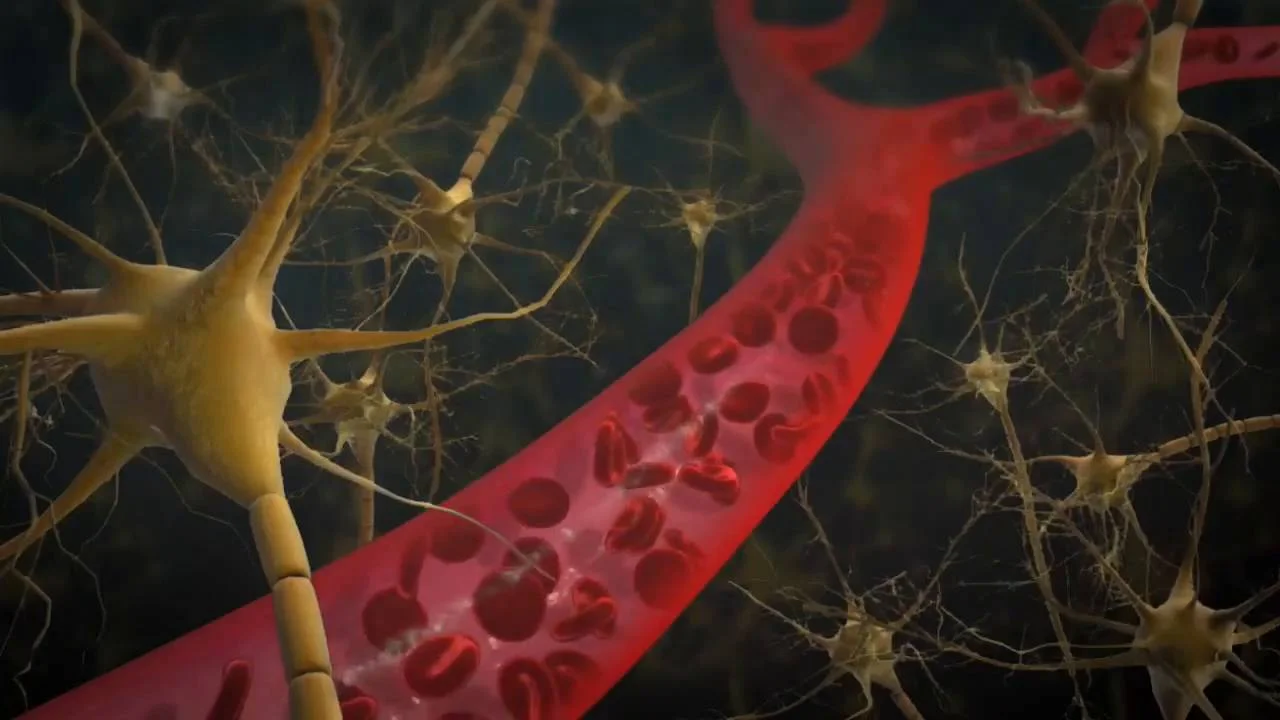

In another third of newborns who get herpes, the central nervous system is affected. This most often shows up at about 2 to 3 weeks of age with symptoms such as irritability, fever, lethargy, poor feeding, or seizures.